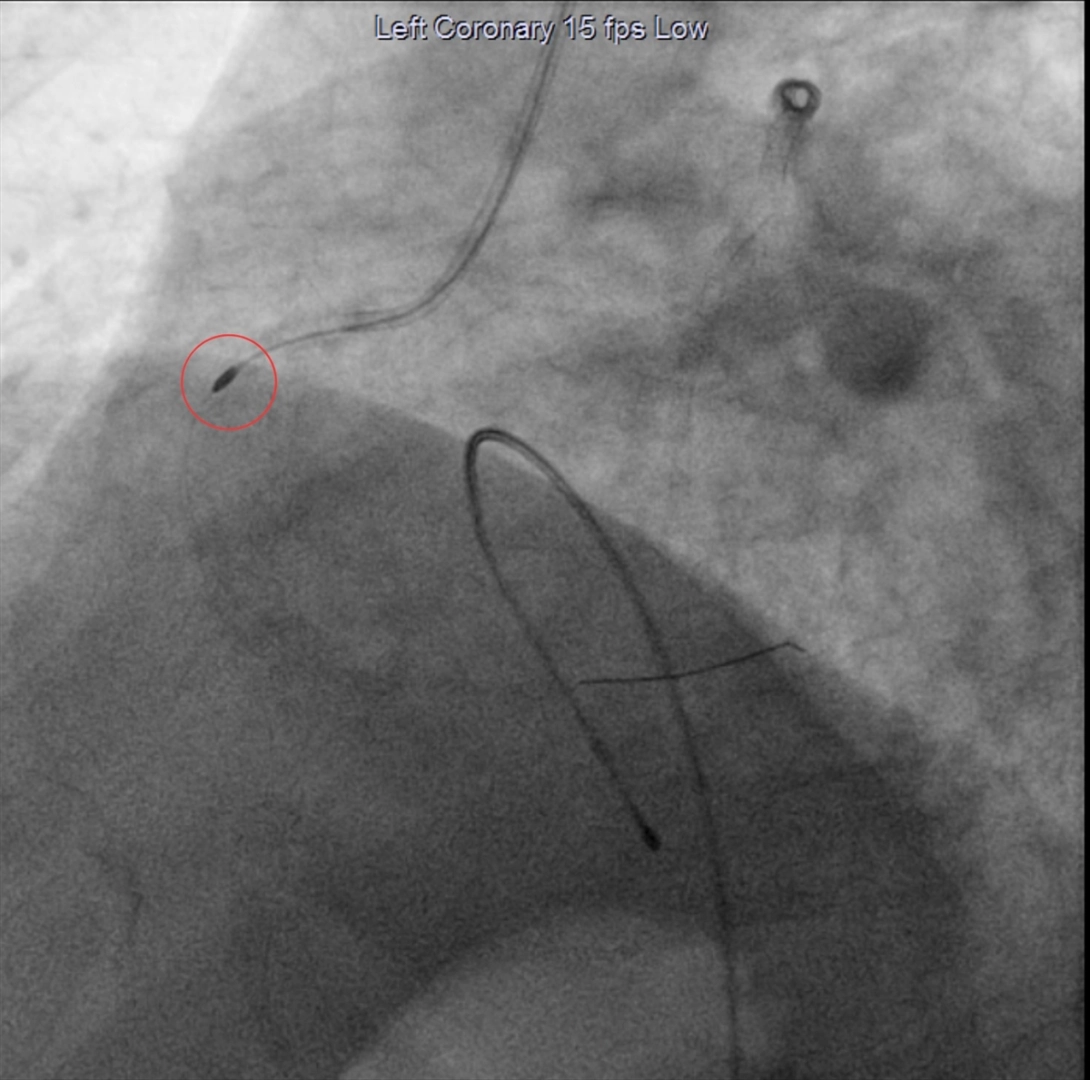

Dünyada yeni olan uygulama ile önce damardaki yoğun kireç, ucu elmas tozuyla kaplı bir damar içi araç ile tıraşlanarak temizleniyor, ardından balon yöntemiyle stent takılıyor.

"Bu hastalarda balon ve stenti geçirmek, stenti optimal şartlarda açmak pek mümkün olmuyor. Bunlarda da şu an yeni bir teknoloji olan rotablasyon işlemi yapıyoruz. Rotablasyon işlemini rotablatör cihazı ile yapıyoruz. Cihazın ucunda elmas tozu kaplı bir uç var. Kendi ekseninde dakikada 150 ile 200 bin devirle dönen cihazı tıpkı bir matkap gibi kireçlenmiş, taşlaşmış olan tıkalı damar bölgesine kasıktan iletiyoruz ve burayı tıraşlayarak kireçli alanı temizliyoruz. Ondan sonra balon ve stent işlemi yapıp hastayı bir gün koroner yoğun bakımda takip ettikten sonra ertesi gün taburcu ediyoruz."

İşlemin anjiyografi laboratuvarında yapıldığını aktaran Polat, "Kasık veya kol damarınızdan işlem yapılabilir. Bu damarlara yerleştirilen kılıflar içerisinden kalp damarlarınıza plastik borular (kateter) yerleştirilir. Bu plastik borular yardımı ile ilgili darlığa rotablatör cihazı ilerletilir. Tıraşlama işlemi sırasında ve sonrasında normal anjiyografi uygulanarak darlığın durumu ve değişiklikler ayrıca incelenir." ifadelerini kullandı.